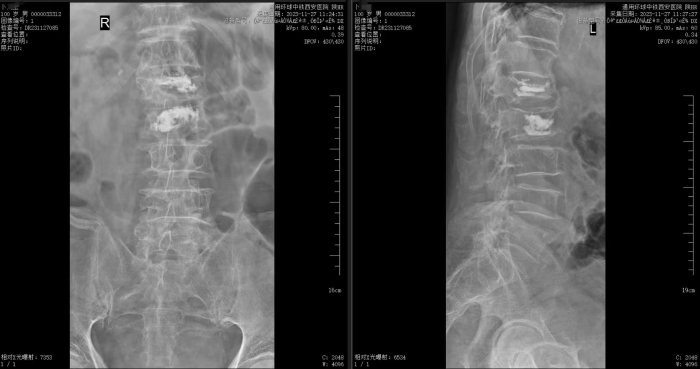

术后影像

经过周密的术前准备,姬传磊团队凭借丰富的经验和娴熟的技术,成功为老人实施了腰1、腰2椎体新鲜压缩性骨折经皮骨水泥填塞、椎体成形术。术后,老人安返病房,生命体征平稳,在医护人员的精心照料下,老人第二天就可以佩戴腰围坐立和下床活动。